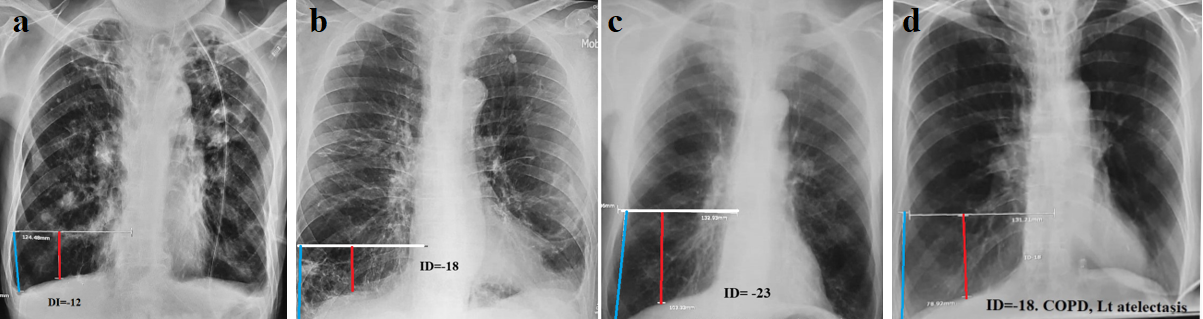

1st group. In 21 patients, the ID was within -7 – (-23) (average -12.2) (Figure 2). The volume of the left lung was increased symmetrically to the right in 18 of them (Figure 2a, b, c). In 3 cases, the volume of the left lung was clearly smaller than the right (Figure 2d).

Figure 2 (a,b,c). Examples of COPD with different heart sizes and chest shapes. They are united by a sharp and uniform increase in lung volume, as indicated by DI values. (d). Severe form of COPD in a patient with a tracheostomy complicated by atelectasis at the base of the left lung. DI= -18.

All radiographs show radiological signs of chronic bronchitis (increased and deformed pulmonary pattern with signs of sclerosis, widening, and poor differentiation of the gates of the lungs). However, these signs are not specific. All radiographs in this group are characterized by a significant increase in lung volume, mathematically defined as DI -5 -23 (average -12.2).